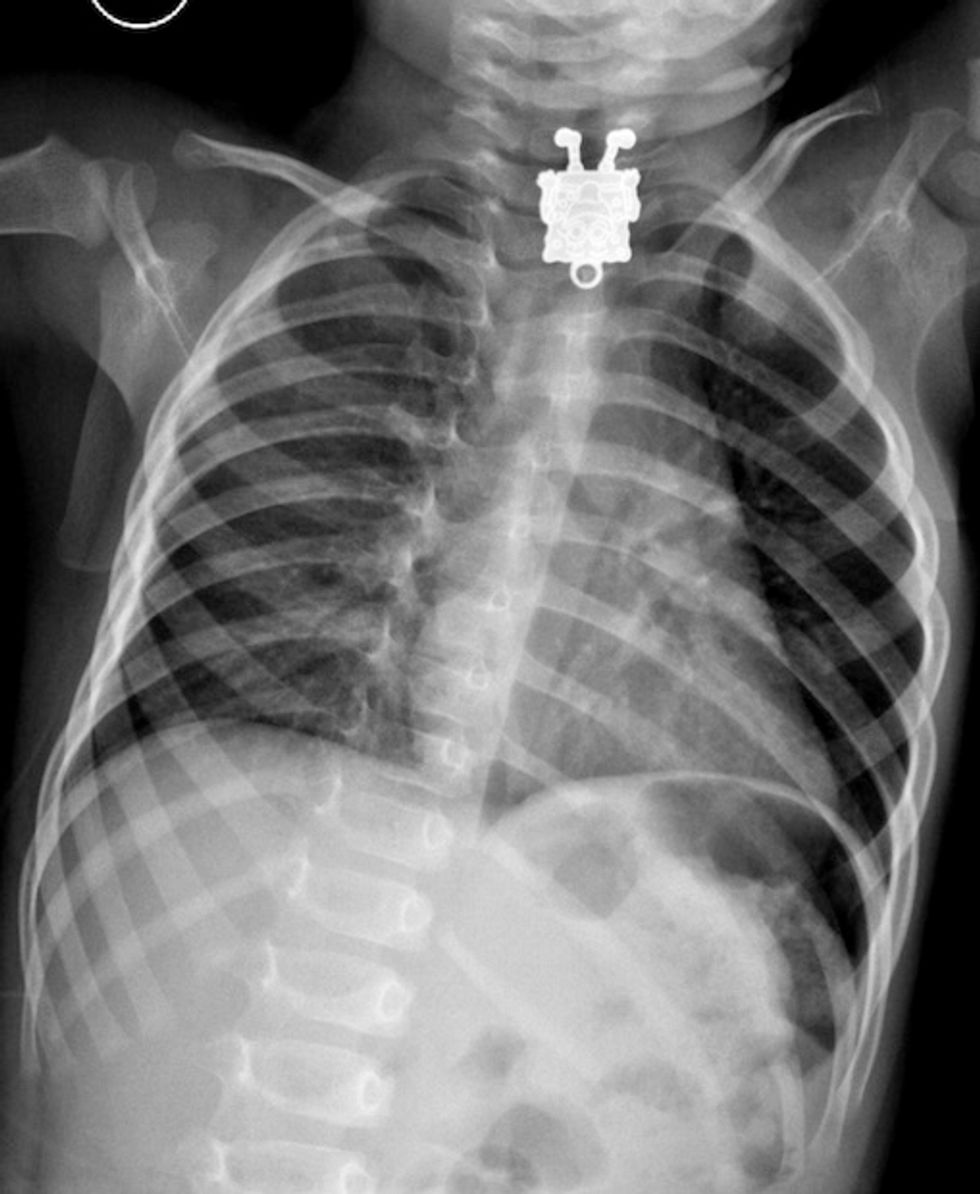

Case courtesy of Dr Ghofran Ageely, Radiopaedia.org

One 16-month-old boy in Saudi Arabia recently swallowed his sister's SpongeBob necklace and was rushed to the hospital. The X-rays of the child's chest taken at King Abdulaziz University Hospital in Jeddah produced some entertaining images. Including one that showed the popular cartoon character smiling at them while sticking out his tongue.

The Daily Mail reported radiologist Dr. Agreely actually screamed when she first saw the image on the scan.